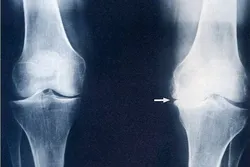

Gonartroza je degenerativno oboljenje kolena koje nastaje kao posledica propadanja hrskavice zgloba, usled čega nastaje formiranje koštanih šiljaka-osteofita.Tako izmenjena struktura tkiva doprinosi stvaranju upale i bola koja stvara velika ograničenja u samom zglobu. Hrskavica zgloba se regeneriše onoliko koliko se troši tokom redovne umerene fizičke aktivnosti, medjutim kada je fizička aktivnost pojačana kao npr. kod sportista gde su prisutne stalne mikrotraume, onda je obnavljanje hrskavice smanjeno.Postoji više faktora rizika koji pospešuju razvoj gonartoze:

je stanje u podmakloj fazi, zadnji stepen gonartoze, gde imamo veliko

ograničenje pokreta, koleno u blagoj fleksiji, savetuje se konsultacija sa

ortopedom-hirurgom o daljem planu lečenja, koji podrazumeva

ugradnju endoproteze- veštačko koleno.